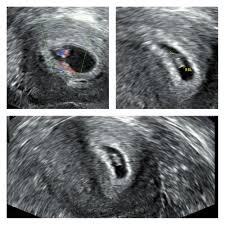

Besonderheiten beim Ultraschall in der 8SSW In der 8Schwangerschaftswoche ist der Kopf noch größer als der gesamte Körper des Embryos. In Ultraschall ist immernoch keine fruchthöhle zu sehen. Das baby ist in der 8 woche 2-3 cm groß und geschlecht wird man sicherlich nicht erkennen können.

Der Dottersack Ein Wichtiger Marker Beim Ultraschall In Der Fruhschwangerschaft Springerlink